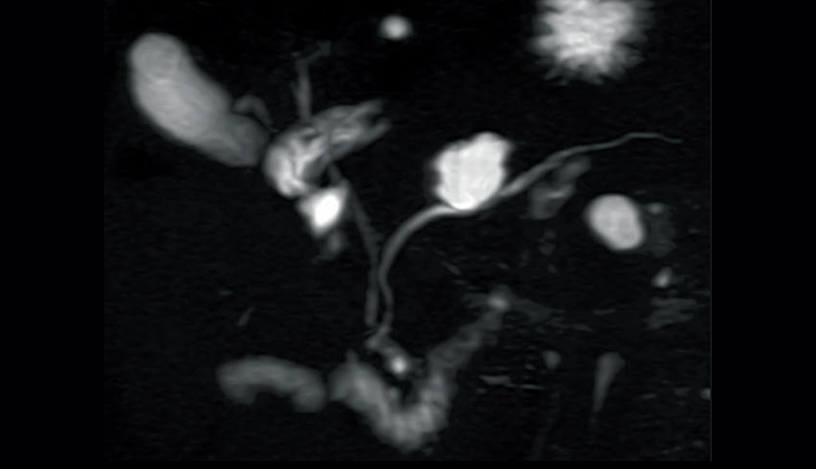

Respiratory-gated MIP image